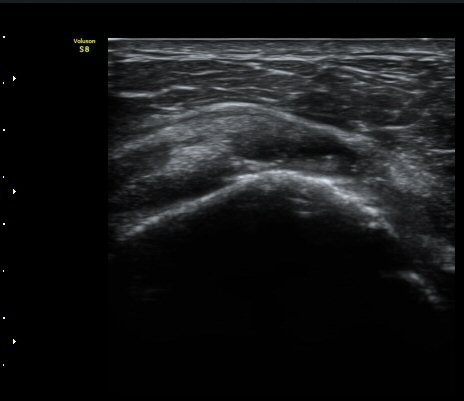

ÃÊÀ½ÆÄ °Ë»ç

À̵ιڱ٠Á¾´Ü¸é°Ë»ç»ó ƯÀÌ ¼Ò°ßÀ» º¸ÀÌÁö ¾ÊÀ¸³ª(±×¸² 1)  ŽÃËÀÚ¸¦ ¾Æ·¡·Î À̵¿ÇÏ´Ï

°ß°©ÇÏ±Ù°Ç ³»Ãø¿¡¼­ ¼ö¾×Àú·ù°¡ °üÂûµÈ´Ù(±×¸² 2).